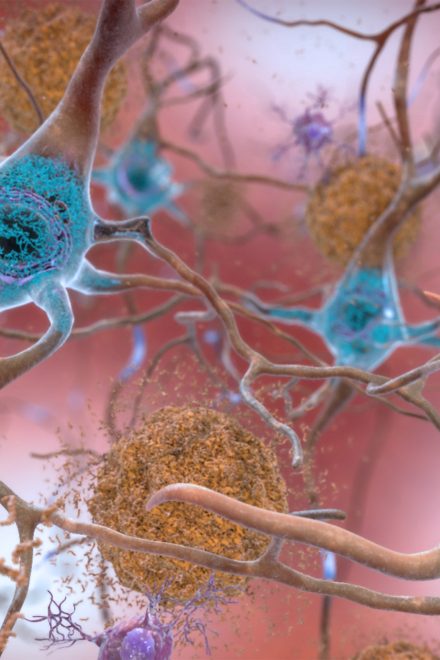

Hallmarks of Alzheimer’s found well before diagnosis

Start of new era for Alzheimer’s treatment

Excessive napping and Alzheimer’s linked in study

Start of new era for Alzheimer’s treatment

Excessive napping and Alzheimer’s linked in study

Staying Healthy February 18, 2024